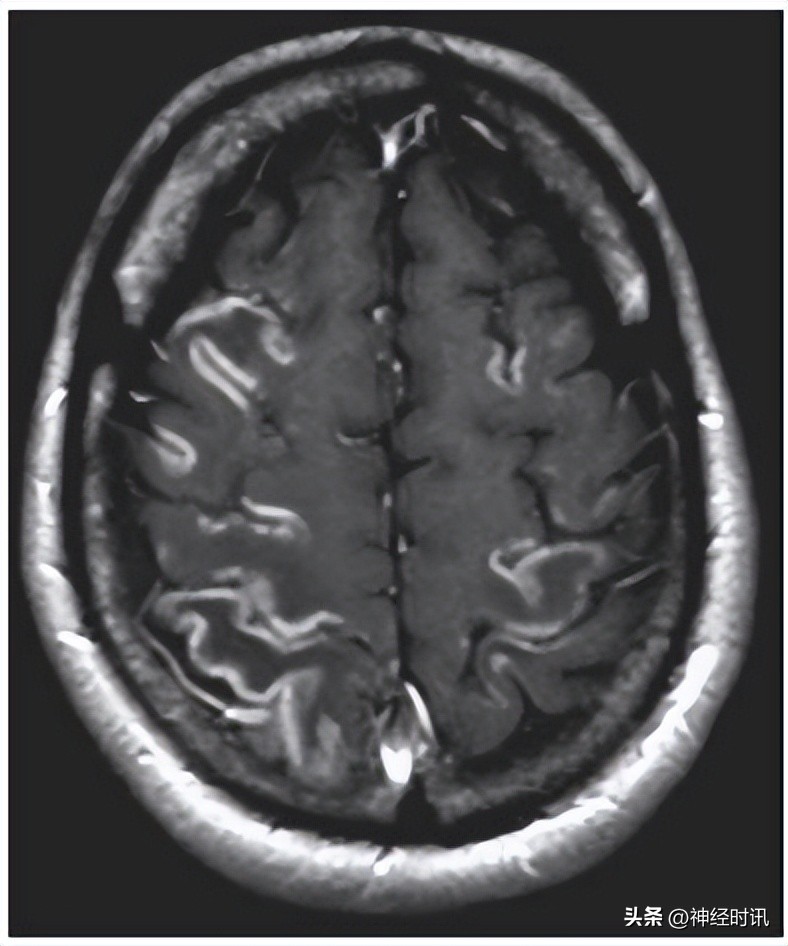

主要的病理改变包括广泛的多灶的或弥漫的皮层坏死及几乎难以避免的海马损伤(图-2)。海马的CAI神经元极不耐受缺血缺氧,这也解释了在短暂的心搏骤停会引起持久的记忆损害。小片状的梗死或神经脱失可出现在基底节、下丘脑或脑干。在某些病例中,广泛双侧的丘脑瘢痕可影响调控觉醒的神经通路,可能是持续植物状态的发病机制。一种特殊类型的缺血缺氧性脑病,又称为分水岭梗死,指发生在相邻供血动脉区之间的边缘带,可造成认知损害,包括视觉认知不能和近端重于远端的肢体乏力。

图-2 缺血缺氧性脑病脑皮质层状坏死。MR T、加权显示与分水岭区分布一致的皮质强化伴层状坏死